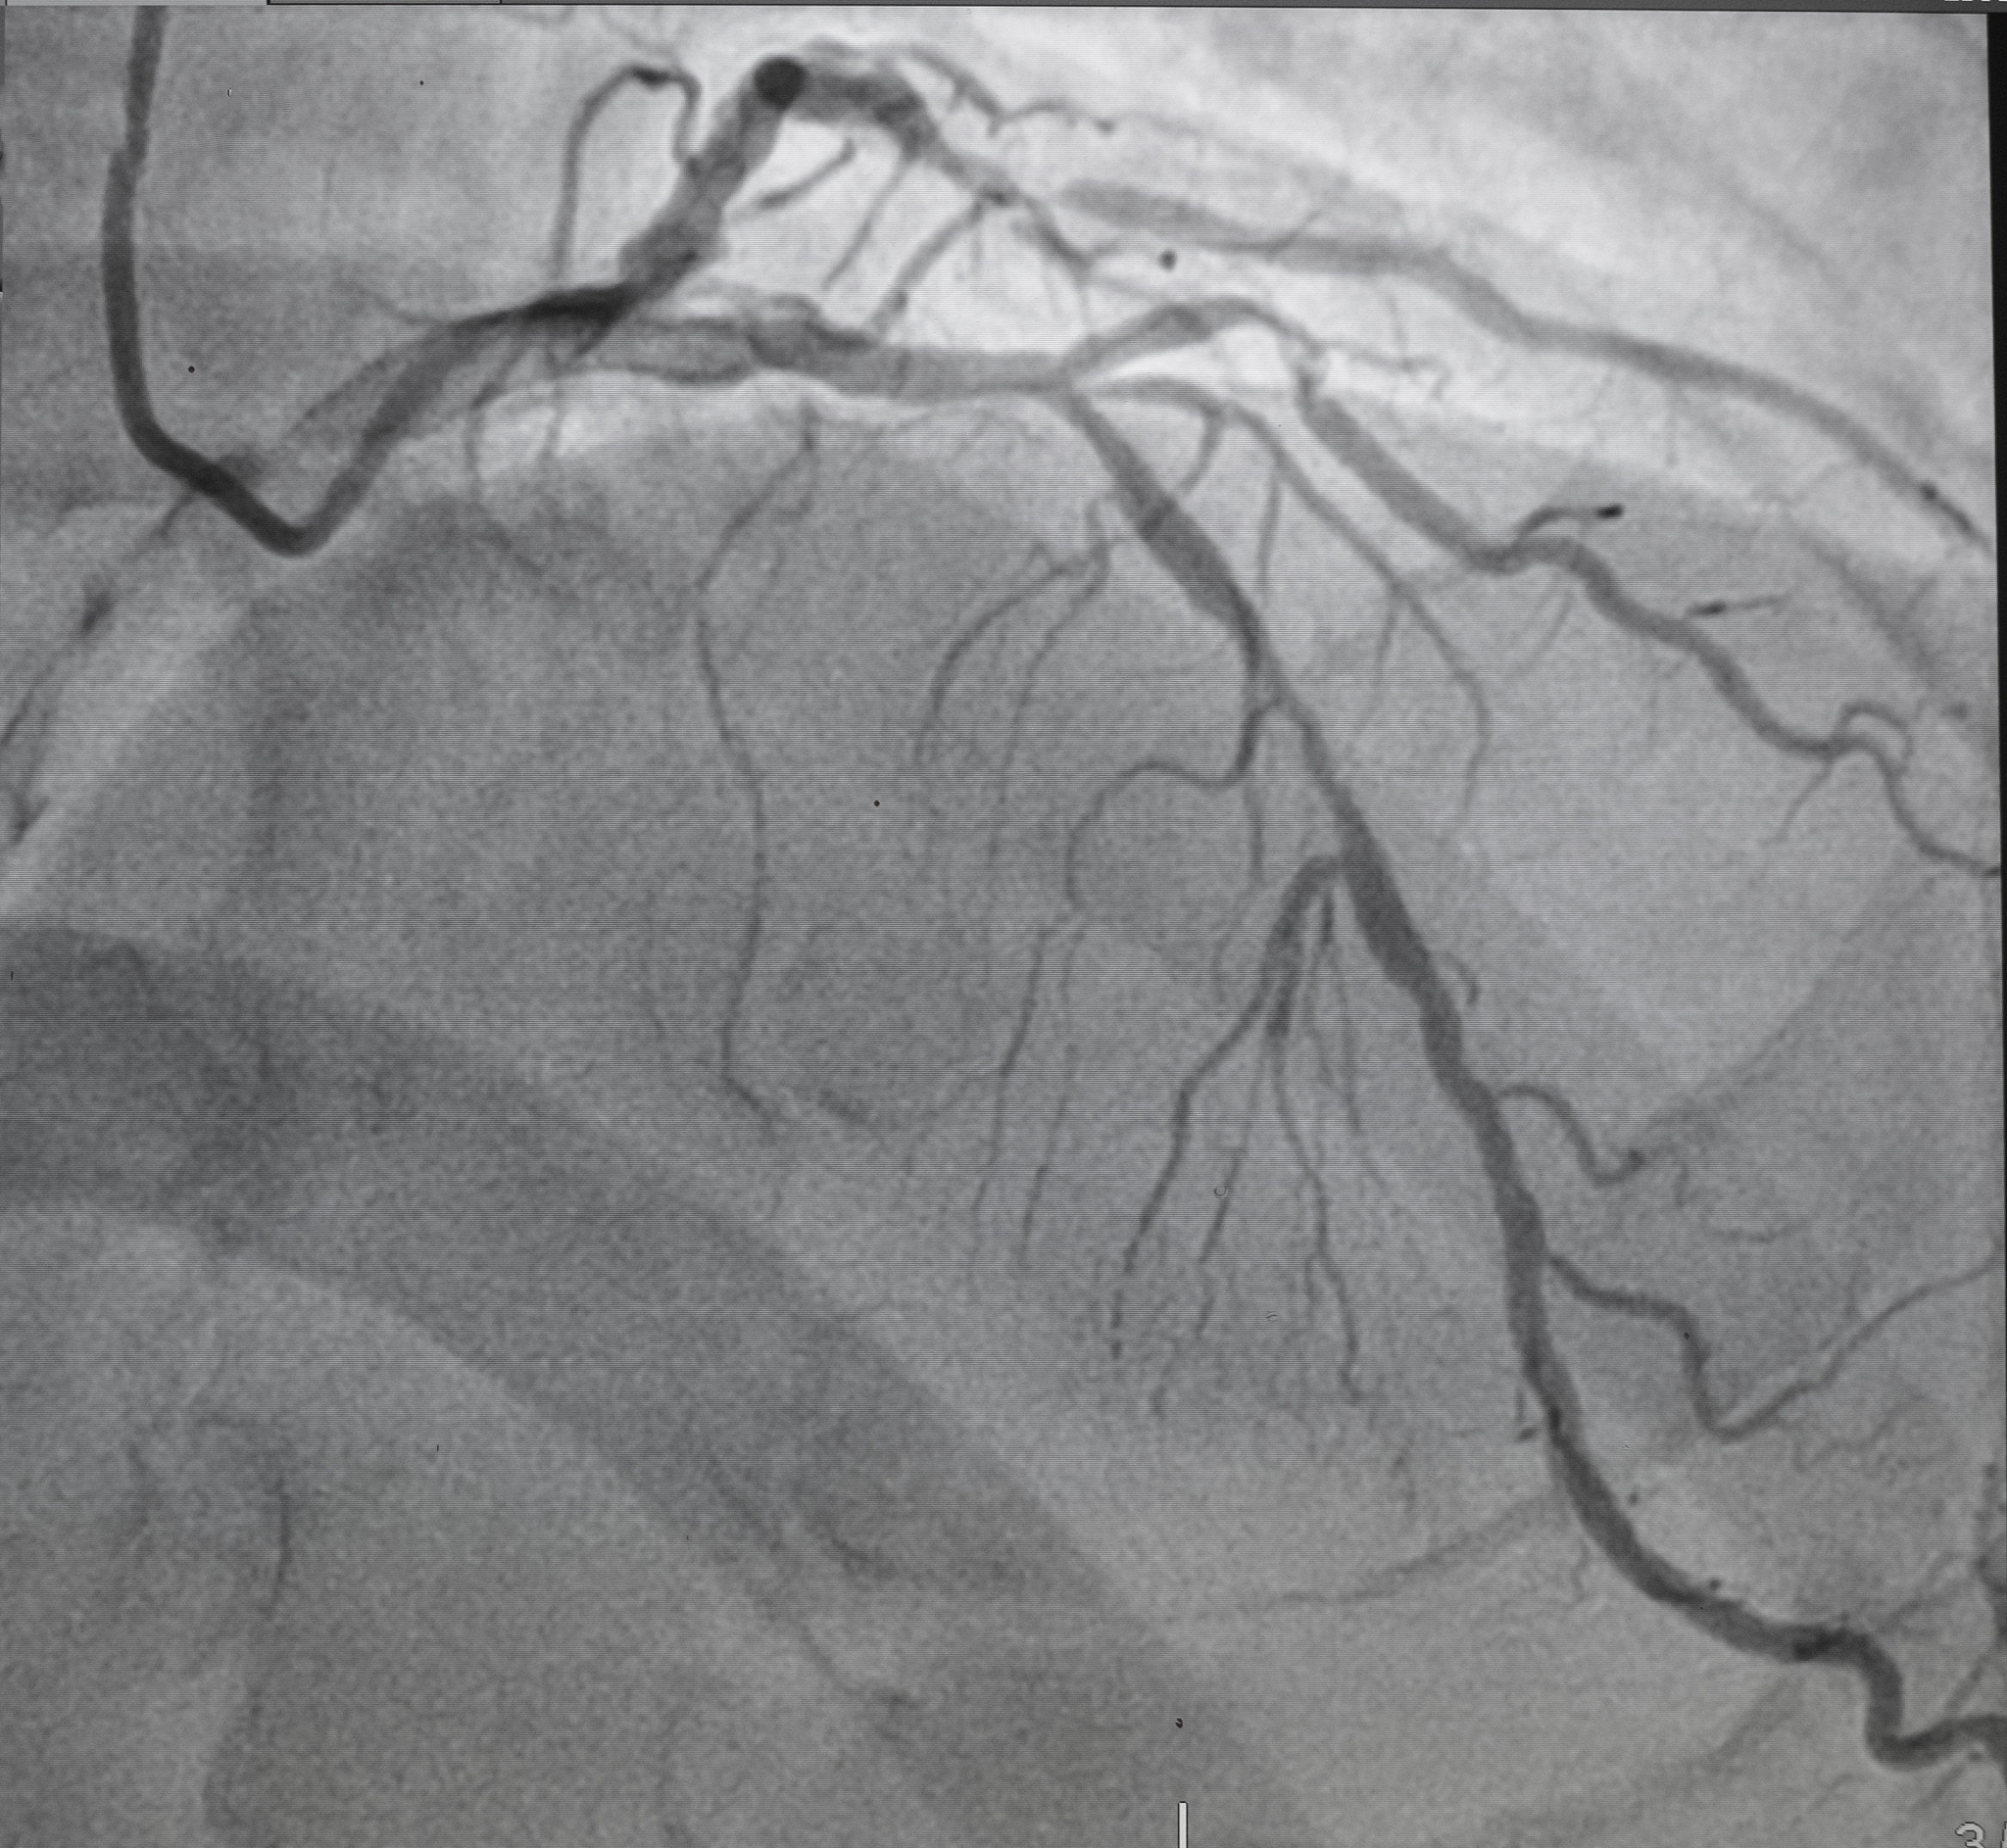

Early and timely diagnosis of vulnerable plaques in the carotid artery that may rupture and cause embolism is crucial, as the presence of free-floating thrombi can lead to more severe strokes and has significant implications for reducing stroke-related morbidity and mortality. Carotid ultrasound imaging is a recommended diagnostic method, due to its simple and convenient operation, real-time monitoring, non-radiation exposure, and bedside examination.